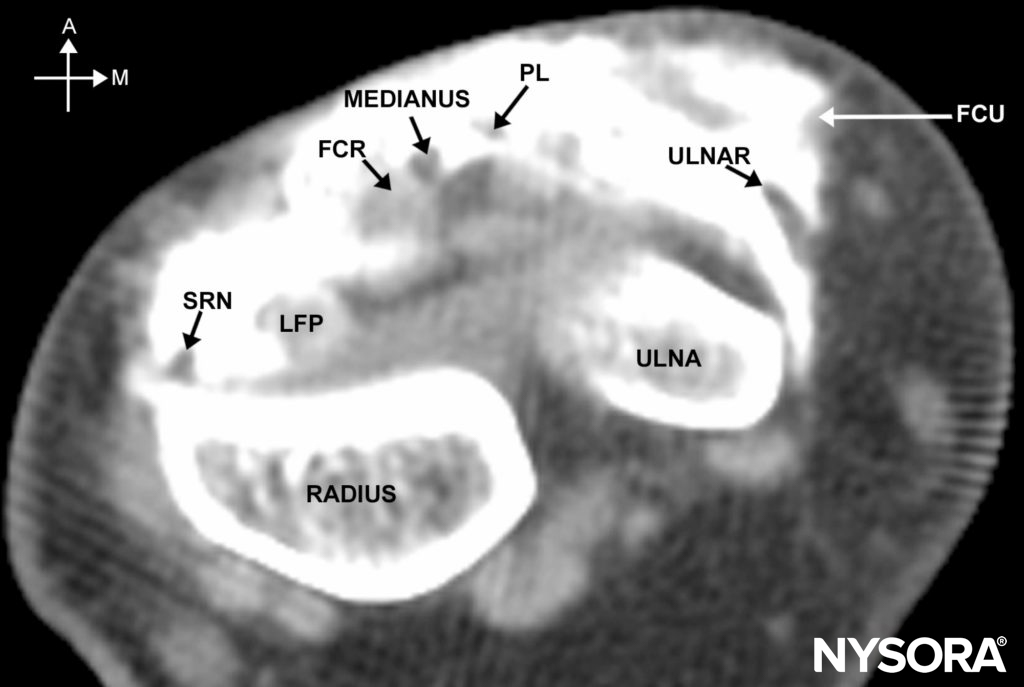

The superficial branch of the radial nerve runs along the medial aspect of the brachioradialis muscle (see Figure 3). It then passes between the tendon of the brachioradialis and radius to pierce the fascia on the dorsal aspect. Just above the styloid process of the radius, it gives off digital branches for the dorsal skin of the thumb, index finger, and lateral half of the middle finger. Several of its branches pass superficially over the anatomic “snuff box.” The median nerve is located between the tendons of the palmaris longus and the flexor carpi radialis (Figure 4; see 2). The palmaris longus tendon is usually the more prominent of the two tendons, and the median nerve passes just lateral to it. The ulnar nerve passes between the ulnar artery and tendon of the flexor carpi ulnaris (see Figures 2 and 4). The tendon of the flexor carpi ulnaris is superficial to the ulnar nerve.

FIGURE 4. Cross-sectional anatomy of the wrist as shown on an MRI scan just above the carpal tunnel. A = anterior, M = medial, SRN = superficial radial nerve, LFP = tendon of the flexor palmaris longus, FCR = flexor carpi radialis, PL = tendon of the palmaris longus, FCU = tendon of the flexor carpi radialis.